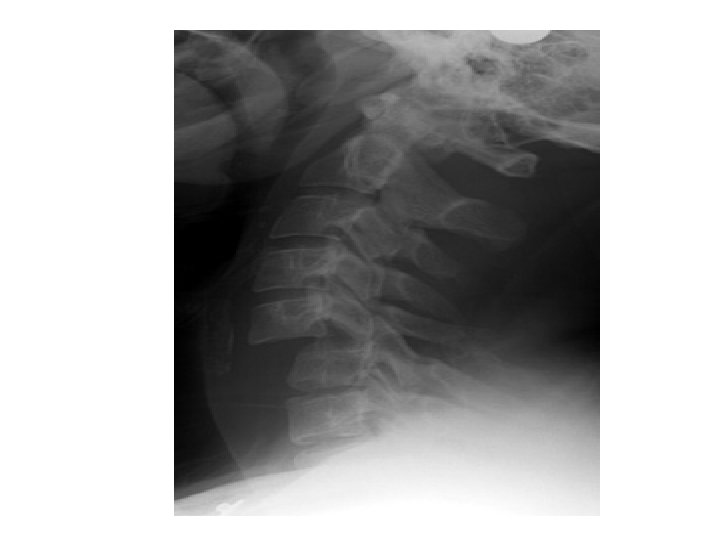

BILATERAL FACET JOINT DISLOCATION • Complete anterior dislocation of the vertebral body • Mechanism – extreme hyperflexion of head and neck without axial compression • Unstable – very high risk of cord damage • Features – – complete anterior dislocation >50% of vertebral body diameter – Disruption of the posterior ligament complex and anterior longitudinal ligament – “Bow tie” appearance of the locked facets.